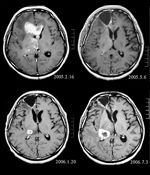

MRI of brain. (Top left) Initial MRI shows a tumor in the right and left frontal lobe as well as the right thalamus. (Top right) MRI after surgery, radiation, and chemotherapy. The tumor has completely disappeared except for slight enhancement adjacent to the surgical margin. (Bottom left) Increase in size of the thalamic tumor two months after stereotactic radiotherapy. (Bottom right) After 6 cycles of TMZ therapy, the thalamic lesion enlarged, and the patient developed dysarthria and hemiparesis. Source: Fujimaki T, Ishii H, Matsuno A, Arai H, Nakagomi T. Effectiveness of interferon-beta and temozolomide combination therapy against temozolomide-refractory recurrent anaplastic astrocytoma.World J Surg Oncol. 2007 Aug 4;5:89.